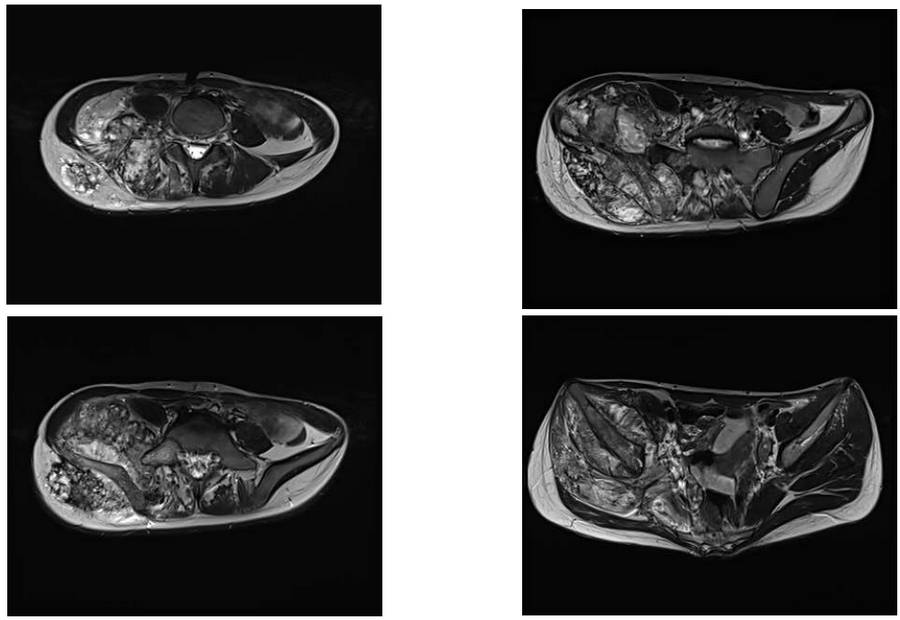

Before surgery: The MRI shows tumor tissue infiltrating the soft tissue, starting from the 4th lumbar vertebra and extending through the sacrum and iliac crest to the hip joint, causing bone destruction.

Before surgery: The CT scan shows an irregularly bordered tumor tissue infiltrating the soft tissue, starting from the 4th lumbar vertebra and extending through the sacrum and iliac crest to the hip joint, causing bone destruction.